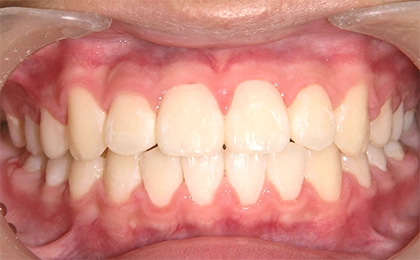

Case2 歯のガタガタ(第1期治療からの継続)

After

治療内容 | 第1期治療で拡大治療+前歯のデコボコ治療をしていたので、表側矯正装置を使用し、非抜歯矯正にて残りの永久歯のガタガタを治療しました。 |

治療のリスク | 第1期治療を行っていなかった場合、抜歯矯正の可能性がありました。 |